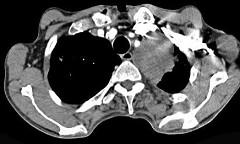

问题 56岁,男,意识错乱情绪不稳定一周,请结合胸片和CT,选出最可能的诊断 ( )

选项 A、韦格肉芽肿 B、胸腺瘤 C、错构瘤 D、胸内甲状腺肿 E、肺癌

答案 E